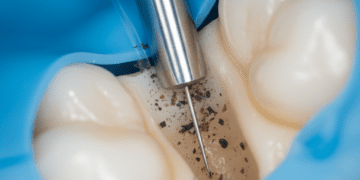

O tratamento visa eliminar a causa da irritação para permitir a recuperação da polpa. As principais condutas são:

- Remoção da cárie: Uma cavidade deve ser cuidadosamente preparada para remover tecido cariado;

- Restauração adequada: Uso de materiais que proporcionem vedação e proteção da polpa, como resinas compostas;